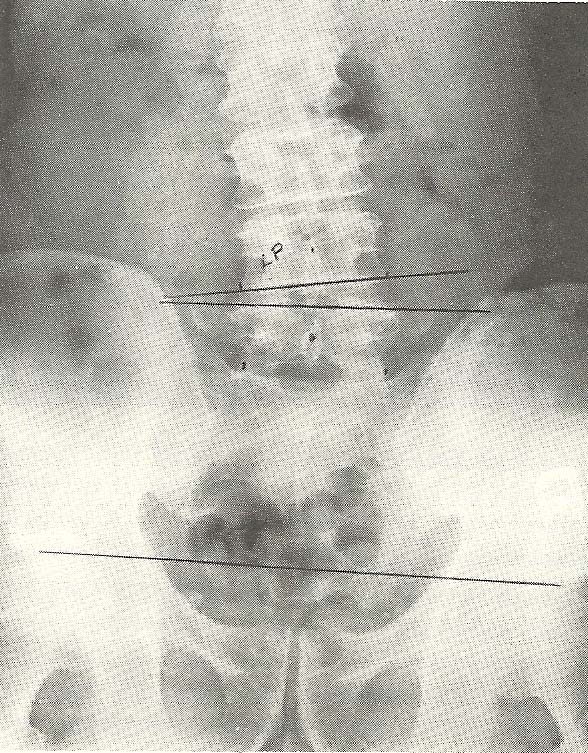

Case Illustrating Classifications C-1, A-1, A-3, and A-8

Frequently several subluxations of different classifications are

demonstrable in spinal films of a specific patient. This case illustrates such

a situation. Alteration in the lumbar lordosis and an antalgic lateral list of

the lumbar vertebrae (both of which represent subluxations classified as C-1:

alteration of the spinal curve secondary to muscular imbalance) are noted.

Concurrently, flexion subluxation (A-1) is noted at L4 L5 and at L5-S1,

narrowing of the disc interspaces (A-8) being evident at both these levels.

Right lateral flexion of L4 upon L5 (A-3) can be suspected from the A-P

film (Fig. 6.69). Wedging of the disc interspace at L4-L5, narrow on the

right, is seen; and although the L5-S1 interspace is only poorly depicted on

the standard A-P film, it may be narrow on the left.

By use of the spot A-P film (Fig. 6.70), making the central ray

approximately parallel to the sacral base, the L5-S1 disc is better seen and

its wedging toward the left is more apparent. This projection gives an

excellent view of the lumbosacral junction and the extent of degenerative

spondylosis. The standard A-P and the lateral film (Fig. 6.71) showed the